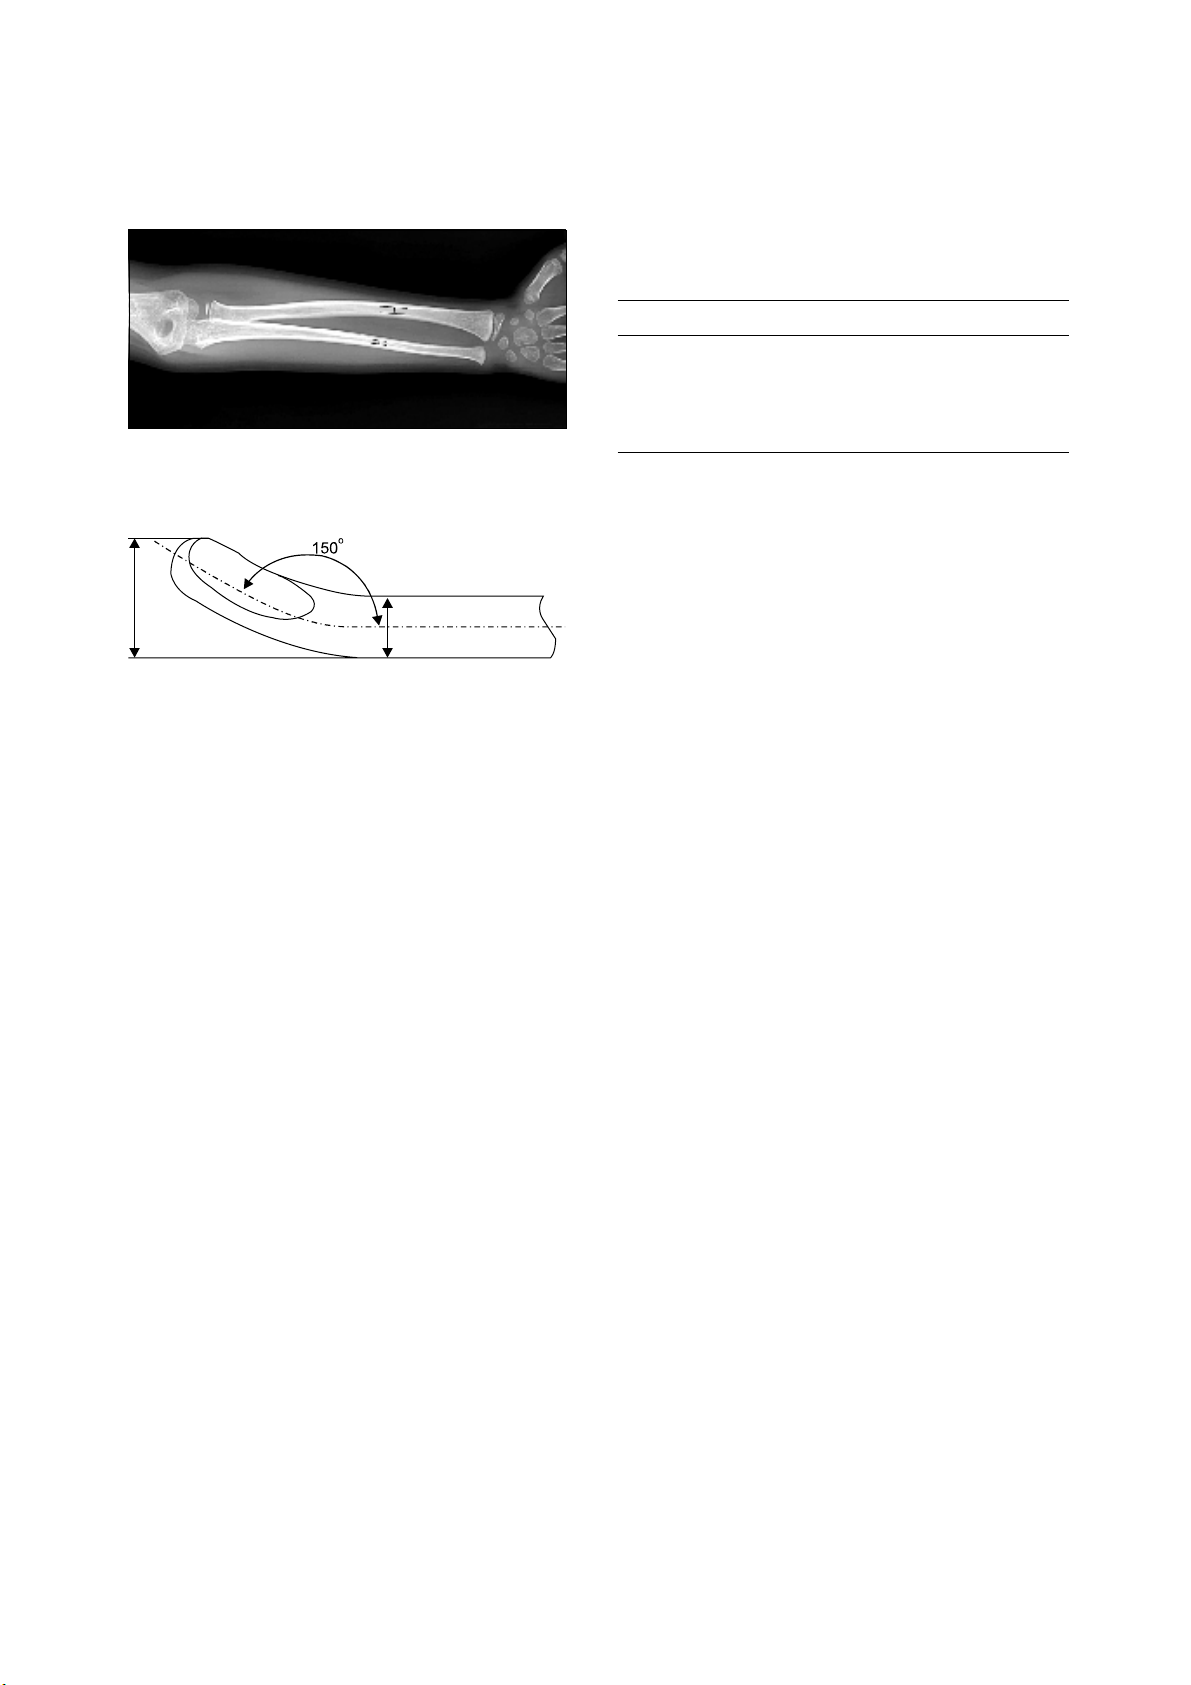

Fig. 1.

The lines show the narrowest points of internal diameter

in the radius and ulna.

Fig. 2.

The passable diameter for the bone is wider than the

diameter of nail itself, with the tip bent for gliding against the

endocortical surface.